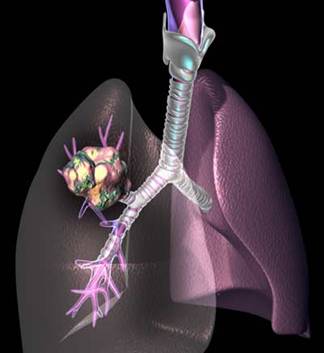

CANCERUL BRONHOPULMONAR

Este o tumoare maligna,cu punct de plecare bronsic.

SIMPTOME simptomele cancerului bronsic,atat cele de debut cat si cele tarzii,sunt in raport cu rectiile pe care le produce tumoarea la nivelul bronhieisi la nivelul parenchimului pulmonar.Unele infectii pot domina tabloul clinic si masca noplasmul.De aceea orice infectie pulmonara persistenta,recidivanta sau rebela la tratament,la un bolnav peste 40 anitrebuie sa sugereze si existenta unui cancer pulmonar.

TRATAMENTULchirurgical estesingurul eficace.Majoritatea bolnavilor ajung prea tirziu la interventia chirurgicala.Tratamentul medical este indicat in formele inoperabiledin cauza metastazelor,varstei inaintate,a complicatiilor.

Cancerul bronhopulmonar este cel mai des intalnit. Chiar si dupa ce au aparut acele mesaje pe pachetele de tigari, numarul bolnavilor nu scade in mod real. De fapt, americanii au ajun la un rezultat abia dupa 10 ani de campanie sustinuta .